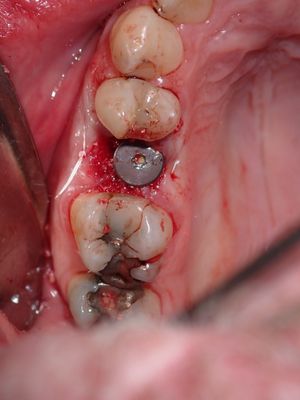

large periapical lesion diagnosed over 11 months ago, cbct scan taken showing no exposure into sinus. Post exo, exposure into sinus membrane, membrane perforation, buccal bone loss about 1.5mm diameter at apex of root. Time taken to clean out socket, placed collagen membrane at apex of socket and against buccal dehiscence, short of sinus floor, packed allograft, bone not displaced into sinus, some pushback, implant placed with excellent stabiltiy, additional bone placed in socket, healing abutment placed.